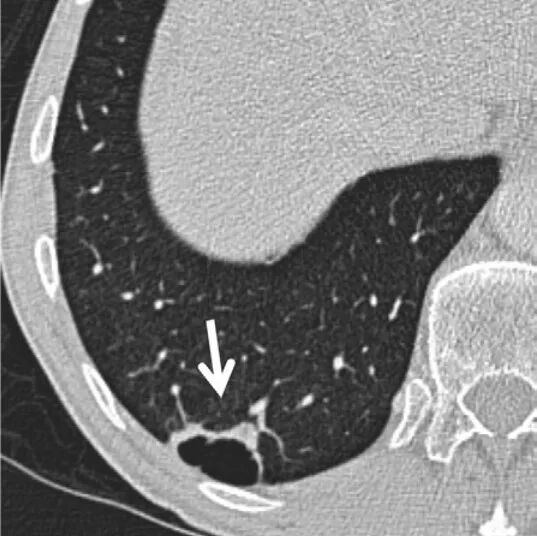

②在普通人群中,当叶间裂旁结节表现出肺内淋巴结典型征象时,通常不建议进行CT随访。